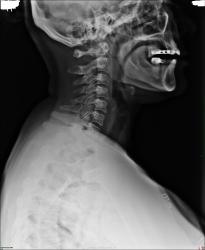

Уважаемые коллеги ,помогите пожалуйста ! Год назад пациентке ( 40 лет )поставили диагноз остеохондроз шейных позвонков. Я сегодня сделала снимок ,остеохондроз грудного отдела не шейного,я так думаю.

Остеохондроз грудного отдела позвоночника выражен больше, чем в шейном отделе.

Трактования дегенеративно-дистрофических изменений настолько многогранны, учитывая отсутствие тяжелых последствий за неправильное трактование картины, что дай рентгенограмму 100 рентгенологам, и увидим заключения от нормы до грубой патологии. А если это касается военкомата, то...А если уже был выставлен диагноз, то попробуйте написать норму, и, тем более, убедить в этом пациента. Как по мне, шея изумительная, а в грудном отделе будет деф. спондилез.

Ето не для военкомата. Я написала шейный отдел норма а грудной остеохондроз , потом выяснилось что она в стационаре лечилась из-за остеохондроза шейного отдела . Вот я решила уточнить я правильно поставила диагноз или нет .